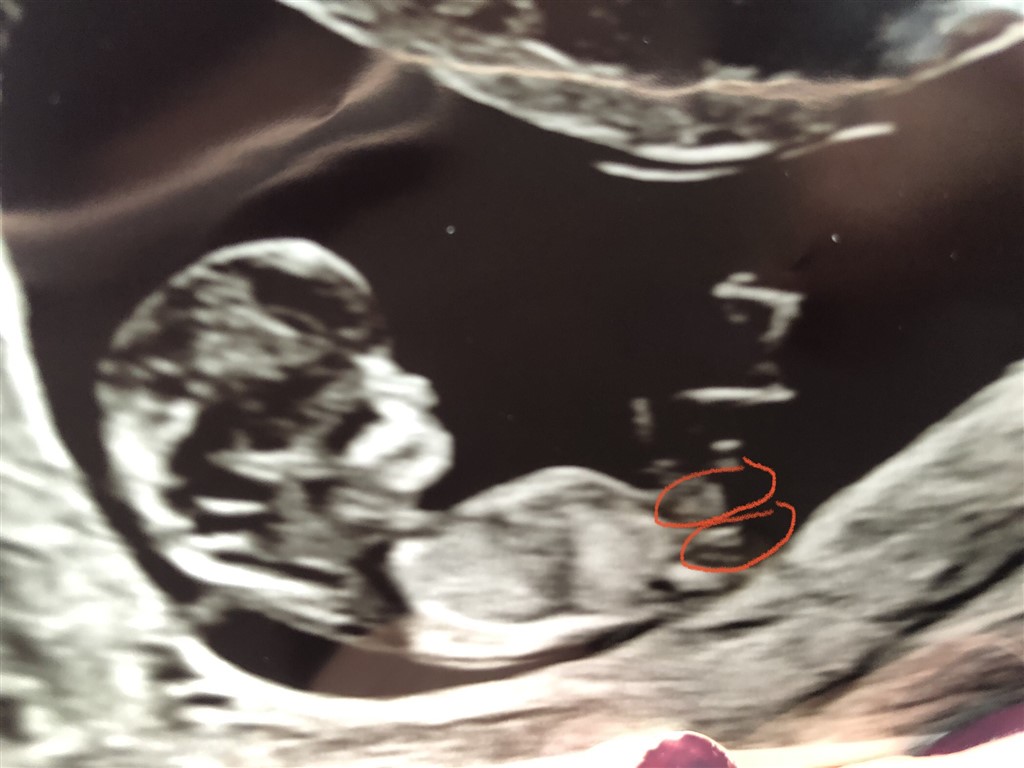

Hvilken af de røde markeringer er nubben, hvis det altså overhovedet er det?

11+5 i dag så ved det endnu er for tidligt til nub-teorien